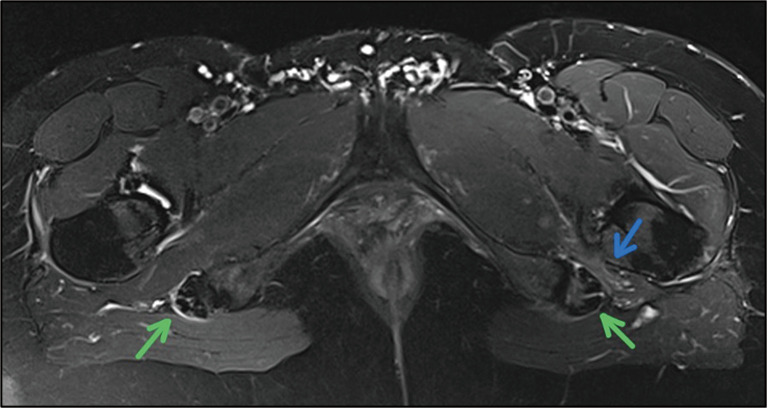

Results: Nerve root contact was demonstrated in only two subjects on the pathology side. Morphological findings on standard MRI with the potential to cause DGS symptoms were inconsistent. Surprisingly, narrowing between the ischium and lesser trochanter of the femur was found in 42% on the symptomatic side. Statistically significant higher mean diffusivity (MD) (P=0.023), radial diffusivity (RD) (P=0.038), and axial diffusivity (AD) (P=0.026) values were observed on the symptomatic side of the SN, indicating edema and microstructural changes. No significant differences were noted in fractional anisotropy (FA) (P=0.913) and normalized quantitative anisotropy (NQA) values (P=0.778). No changes in diffusivity were observed at the LSP level. Twelve subjects (63%) showed increased latency (>1.2 ms) or complete disappearance of the H-reflex when using modified muscle position/activation on the symptomatic side. Clinical tests showed inconclusive results.